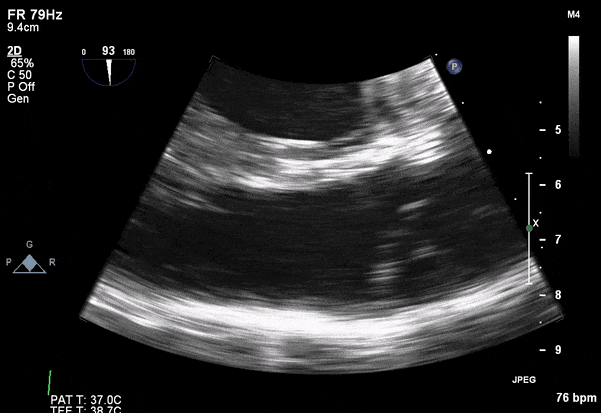

Transesophageal Images

Case 2 (Pulmonic Valve IE)